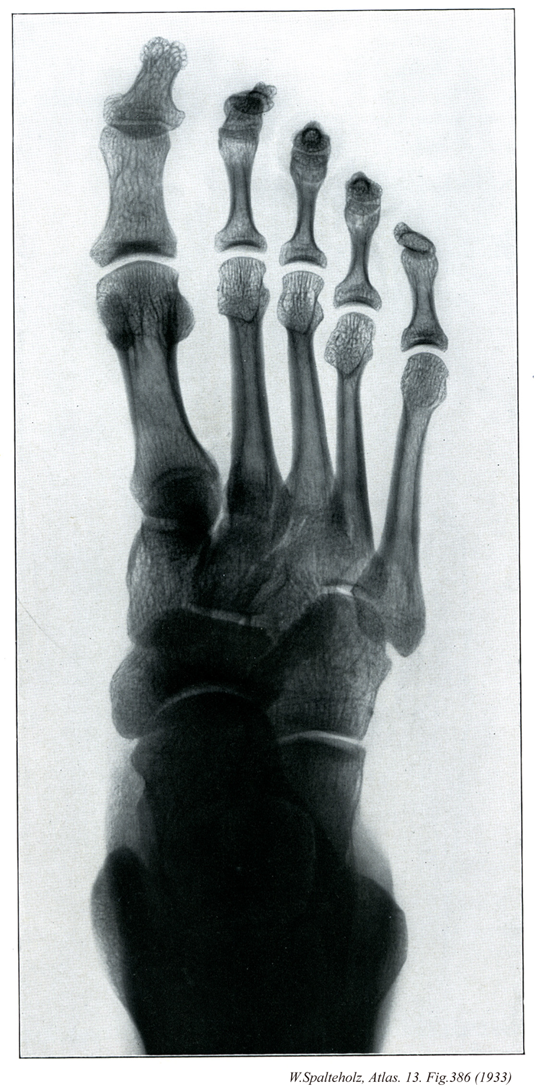

【Foot

足

Pes】

→(足根部、中足部および趾(足の指)にわけられる。足根部は足根骨(7個)、中足部は中足骨(5本)、趾は趾骨(14個)が基礎となっている。皮膚節において第四腰神経、第五腰神経、第一仙骨神経のレベル)